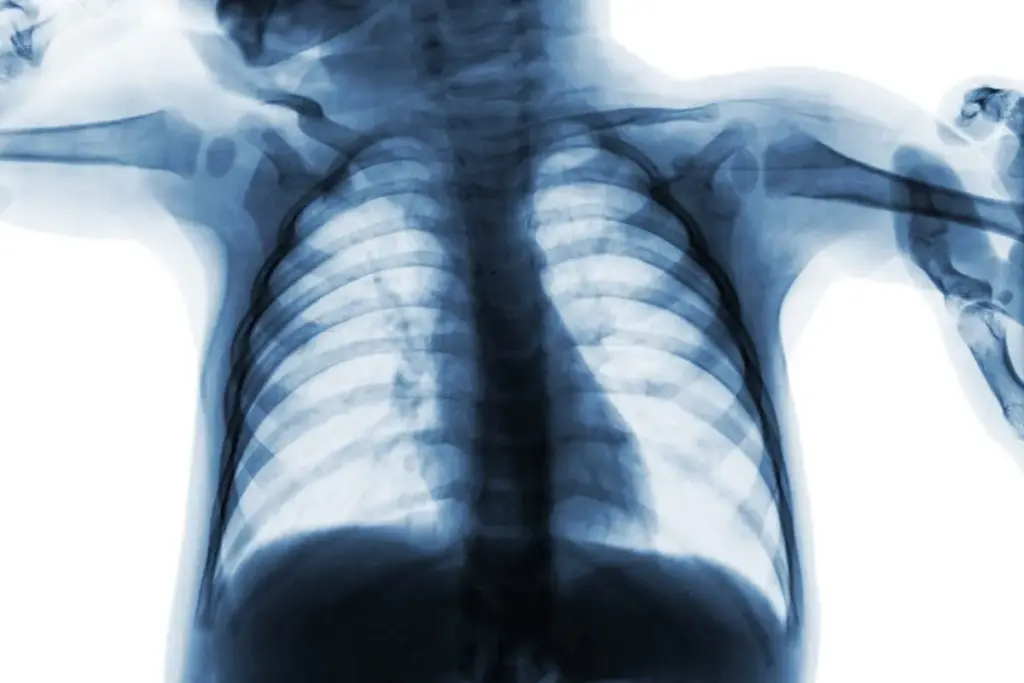

Chest X-Ray (CXR)

A chest X-ray is not required for every child with RSV, but it is necessary if the child is severely ill or if the fever is very high.

• RSV Findings: Common signs include hyperinflation (the lungs look “too big” because air is trapped) and peribronchial thickening. It also helps rule out bacterial pneumonia or a collapsed lung (atelectasis).

It means air enters the lungs but cannot easily escape because of mucus, causing the lungs to appear overfilled on the X-ray.